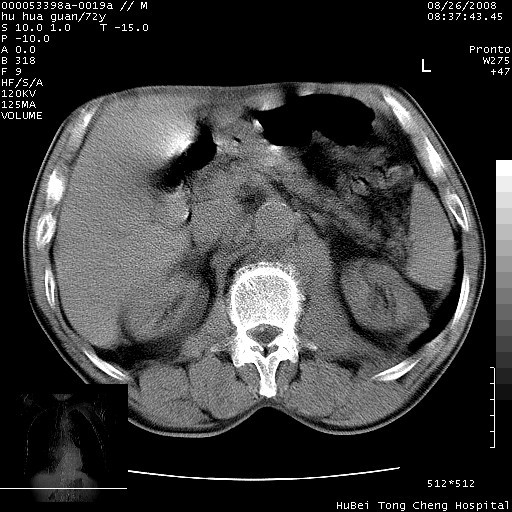

可以明确的说。肯定不是主动脉夹层破裂出血!考虑为淋巴瘤或间叶组织来源的恶性肿瘤可能性大。右肺小结节建议薄层观察,如能发现恶性征象,那椎前改变就考虑为转移所致。至于双侧少量胸水乃静脉血回流受阻所致。

图像及窗宽窗位均不理想。周围性肺癌/胸腔积液/纵隔积液。

1、右肺周围性肺癌、胸腔积液(双)

2、建议食道吞钡和增强检查排除食道和主动脉病变

3、后纵隔淋巴类肿瘤

1、右上肺结节病变,肺泡癌不除外,请随诊;左下肺近后纵隔病变,考虑纵隔型肺癌侵犯大血管可能;

2、右下肺背段少许炎症,双侧胸腔积液,右下肺纤维索条。

降主动脉前移位,后纵隔占位

后纵隔占位,降主动脉前移位;双侧胸腔积液;应排外食管病变侵犯血管可能;